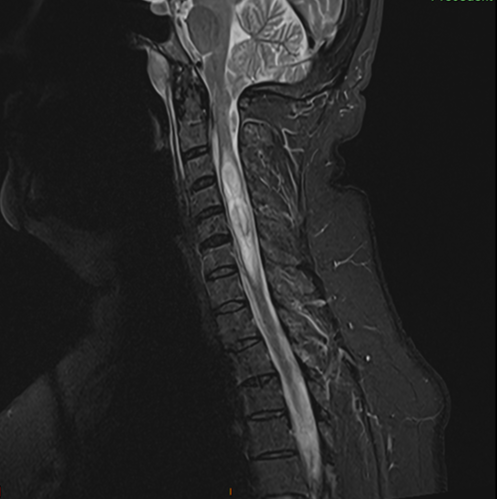

Malformation d’Arnold Chiari avec syringomyélie, préopératoire

Celle-ci est souvent associée à des troubles de la circulation du liquide cérébro-spinal et peut aboutir à une accumulation de liquide notamment au niveau médullaire (=syringomyélie).

Pré et post opératoire, disparition de l’engagement des tonsilles cérébelleuses et diminution de la syringomyélie